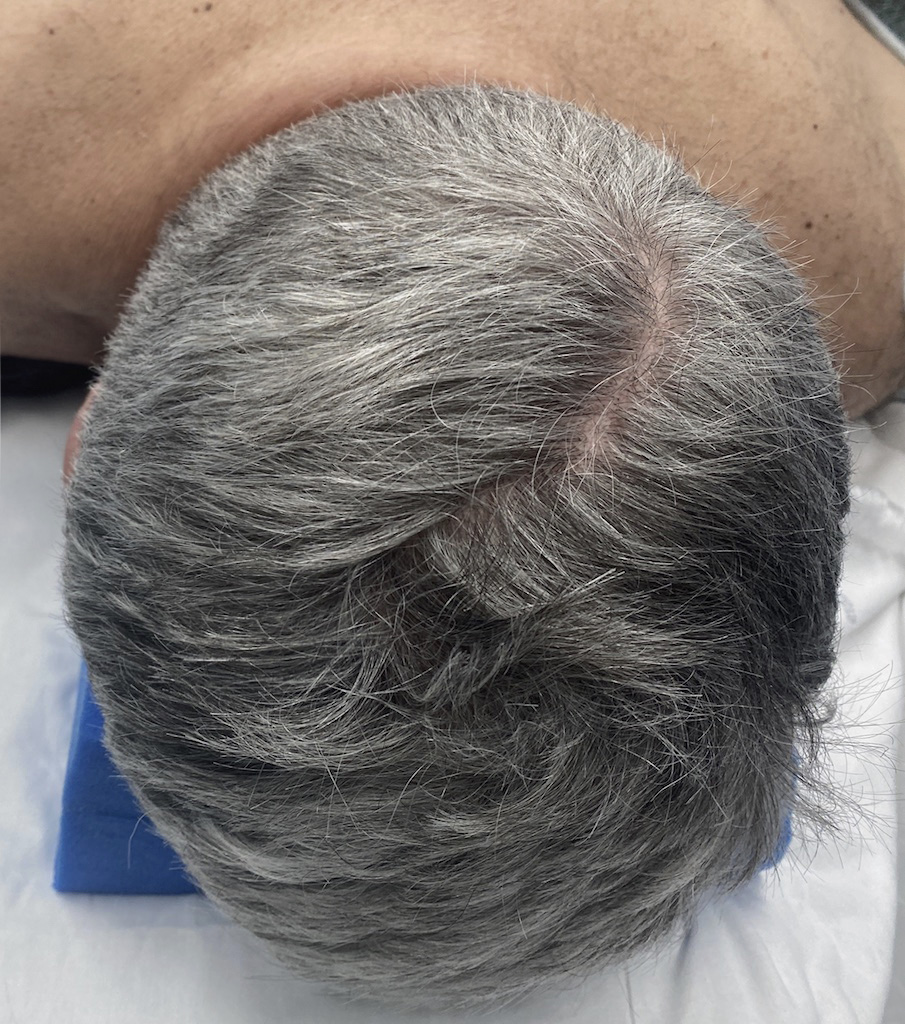

Desire for reduction of prominent occipital knob deformity.

Intraoperative result from occipital knob skull reduction through a direct small scalp incision.

Desire for reduction of prominent occipital knob deformity.

Intraoperative result from occipital knob skull reduction through a direct small scalp incision.